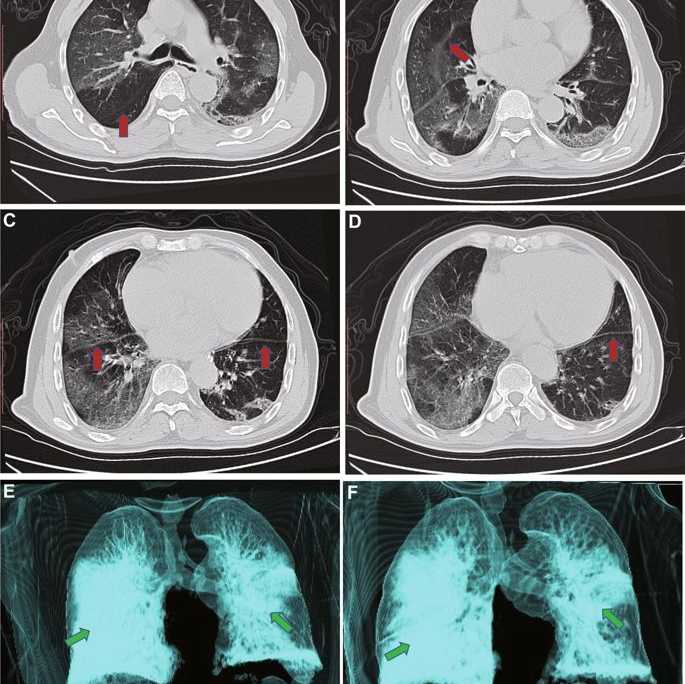

Как выглядит COVID-19 на томограмме

Можно выделить ряд характерных признаков, которые обнаруживаются на томограмме после КТ в случае наличия коронавируса:

- круглые по форме очаги, которые иногда поражают значительные площади и соединяются между собой;

- области между легочными дольками становятся более толстыми и даже чем-то напоминают брусчатку, которую используют на дорожном покрытии;

- при коронавирусе нередко наблюдается двустороннее поражение;

- если ориентироваться на область, где находится основной бронх, то очаги обычно располагаются вдали от него.

Очаги зачастую можно увидеть там, где располагается плевральная оболочка. Характерно и их присутствие в нижних отделах, где проходят кровеносные сосуды.

При атипичной вирусной пневмонии, спровоцированной COVID-19, проходимость воздуха в легких сохраняется и никоим образом не страдает. Практически одинаковый легочной рисунок как в здоровых тканях легких, так и в пораженных вирусом областях тоже характерный признак коронавирусной инфекции.